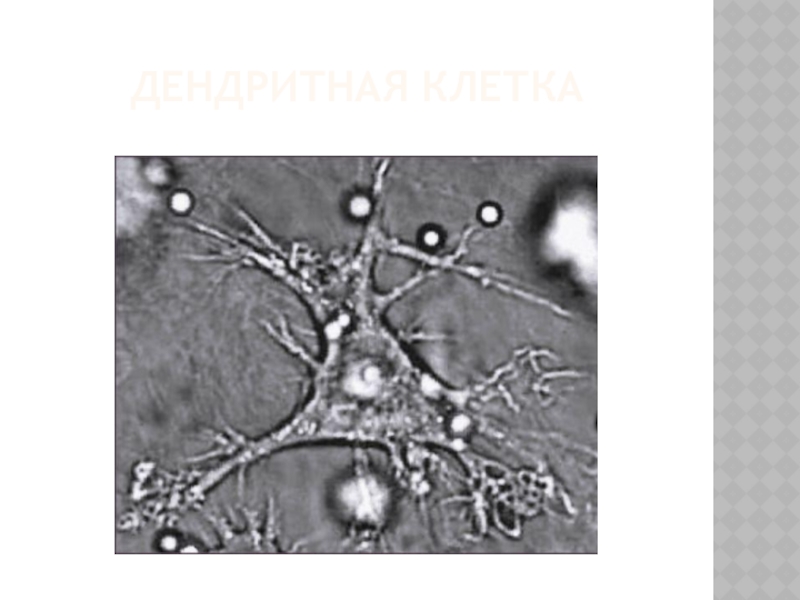

64.Иммунные клетки, их кооперация (Т-, В-лимфоциты, макрофаги).